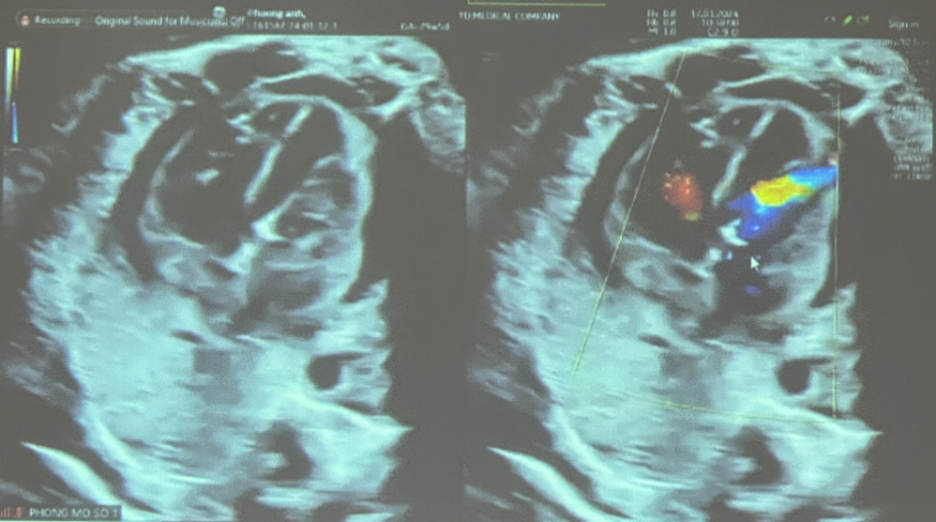

Nhận thấy điều đó, cùng với sự hỗ trợ của cố bác sĩ Bruno Schaub (Pháp), bác sĩ Nguyễn Ngọc Tú đã đi sâu vào lĩnh vực can thiệp thai nhi trong buồng tử cung, thực hiện thành công nhiều kỹ thuật rất khó như:

- Truyền máu thai nhi trong tử cung

- Chọc hút – dẫn lưu dịch màng phổi thai nhi

- Can thiệp bàng quang thai nhi

- Truyền ối, đặt shunt dẫn lưu

- Prenatal Detection of Complete Atrioventricular Septal Defect… – BioMedical 2021